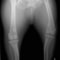

■ 症例20 ポメラニアン 8ヶ月 1.8kg

左右膝蓋骨脱臼 グレードⅢ

2ヶ月前から間欠的跛行が認められ、両膝の膝蓋骨脱臼整復術を行った。

手技は縫工筋及び内側広筋の解放、脛骨粗面の外側転位、滑車ブロック形造溝術、内外側関節包の縫縮を選択し実施した。

右側の膝蓋骨脱臼は上記手技で整復されたものの、左側はそれのみでは膝蓋骨が浮く様子が認められた。その為、PDS縫合糸にて膝蓋靱帯を1糸のみ縫合し、靱帯の縫縮を行った。

膝蓋骨脱臼は膝関節における膝蓋骨の内外側の脱臼と定義されるが、時として単純な内外の脱臼ではなく、膝蓋骨が大きく前方に浮き上がるように脱臼する場合がある。特にトイプードルやポメラニアンといった犬種に多く認められる。

内側脱臼に加えて前方への浮き上がりを矯正する為に、従来より脛骨粗面転移により膝蓋靭帯を外方と下方に引っ張り、固定する方法を選択する。膝蓋骨の前方への浮き上がりが軽度の場合は、従来法ではなく関節包の縫縮で対応していた。しかし、一部の症例で膝蓋骨の動きが悪くなり伸展機構が円滑に機能せずロボット様歩行になるケースがあった。

その為、膝蓋靭帯自体を縫縮する方法を採用した。この方法により、膝関節の伸展機構を妨げず膝蓋骨の軽度の浮きを矯正することが可能となった。

本症例の経過は良好である